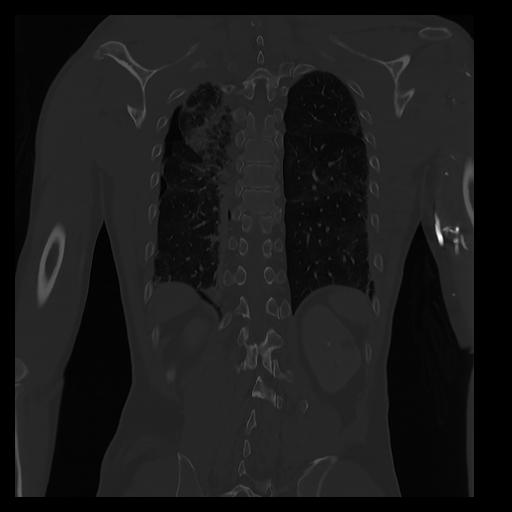

32 PULMON,CE,Coronal,3.000,PULMON,Coronal,